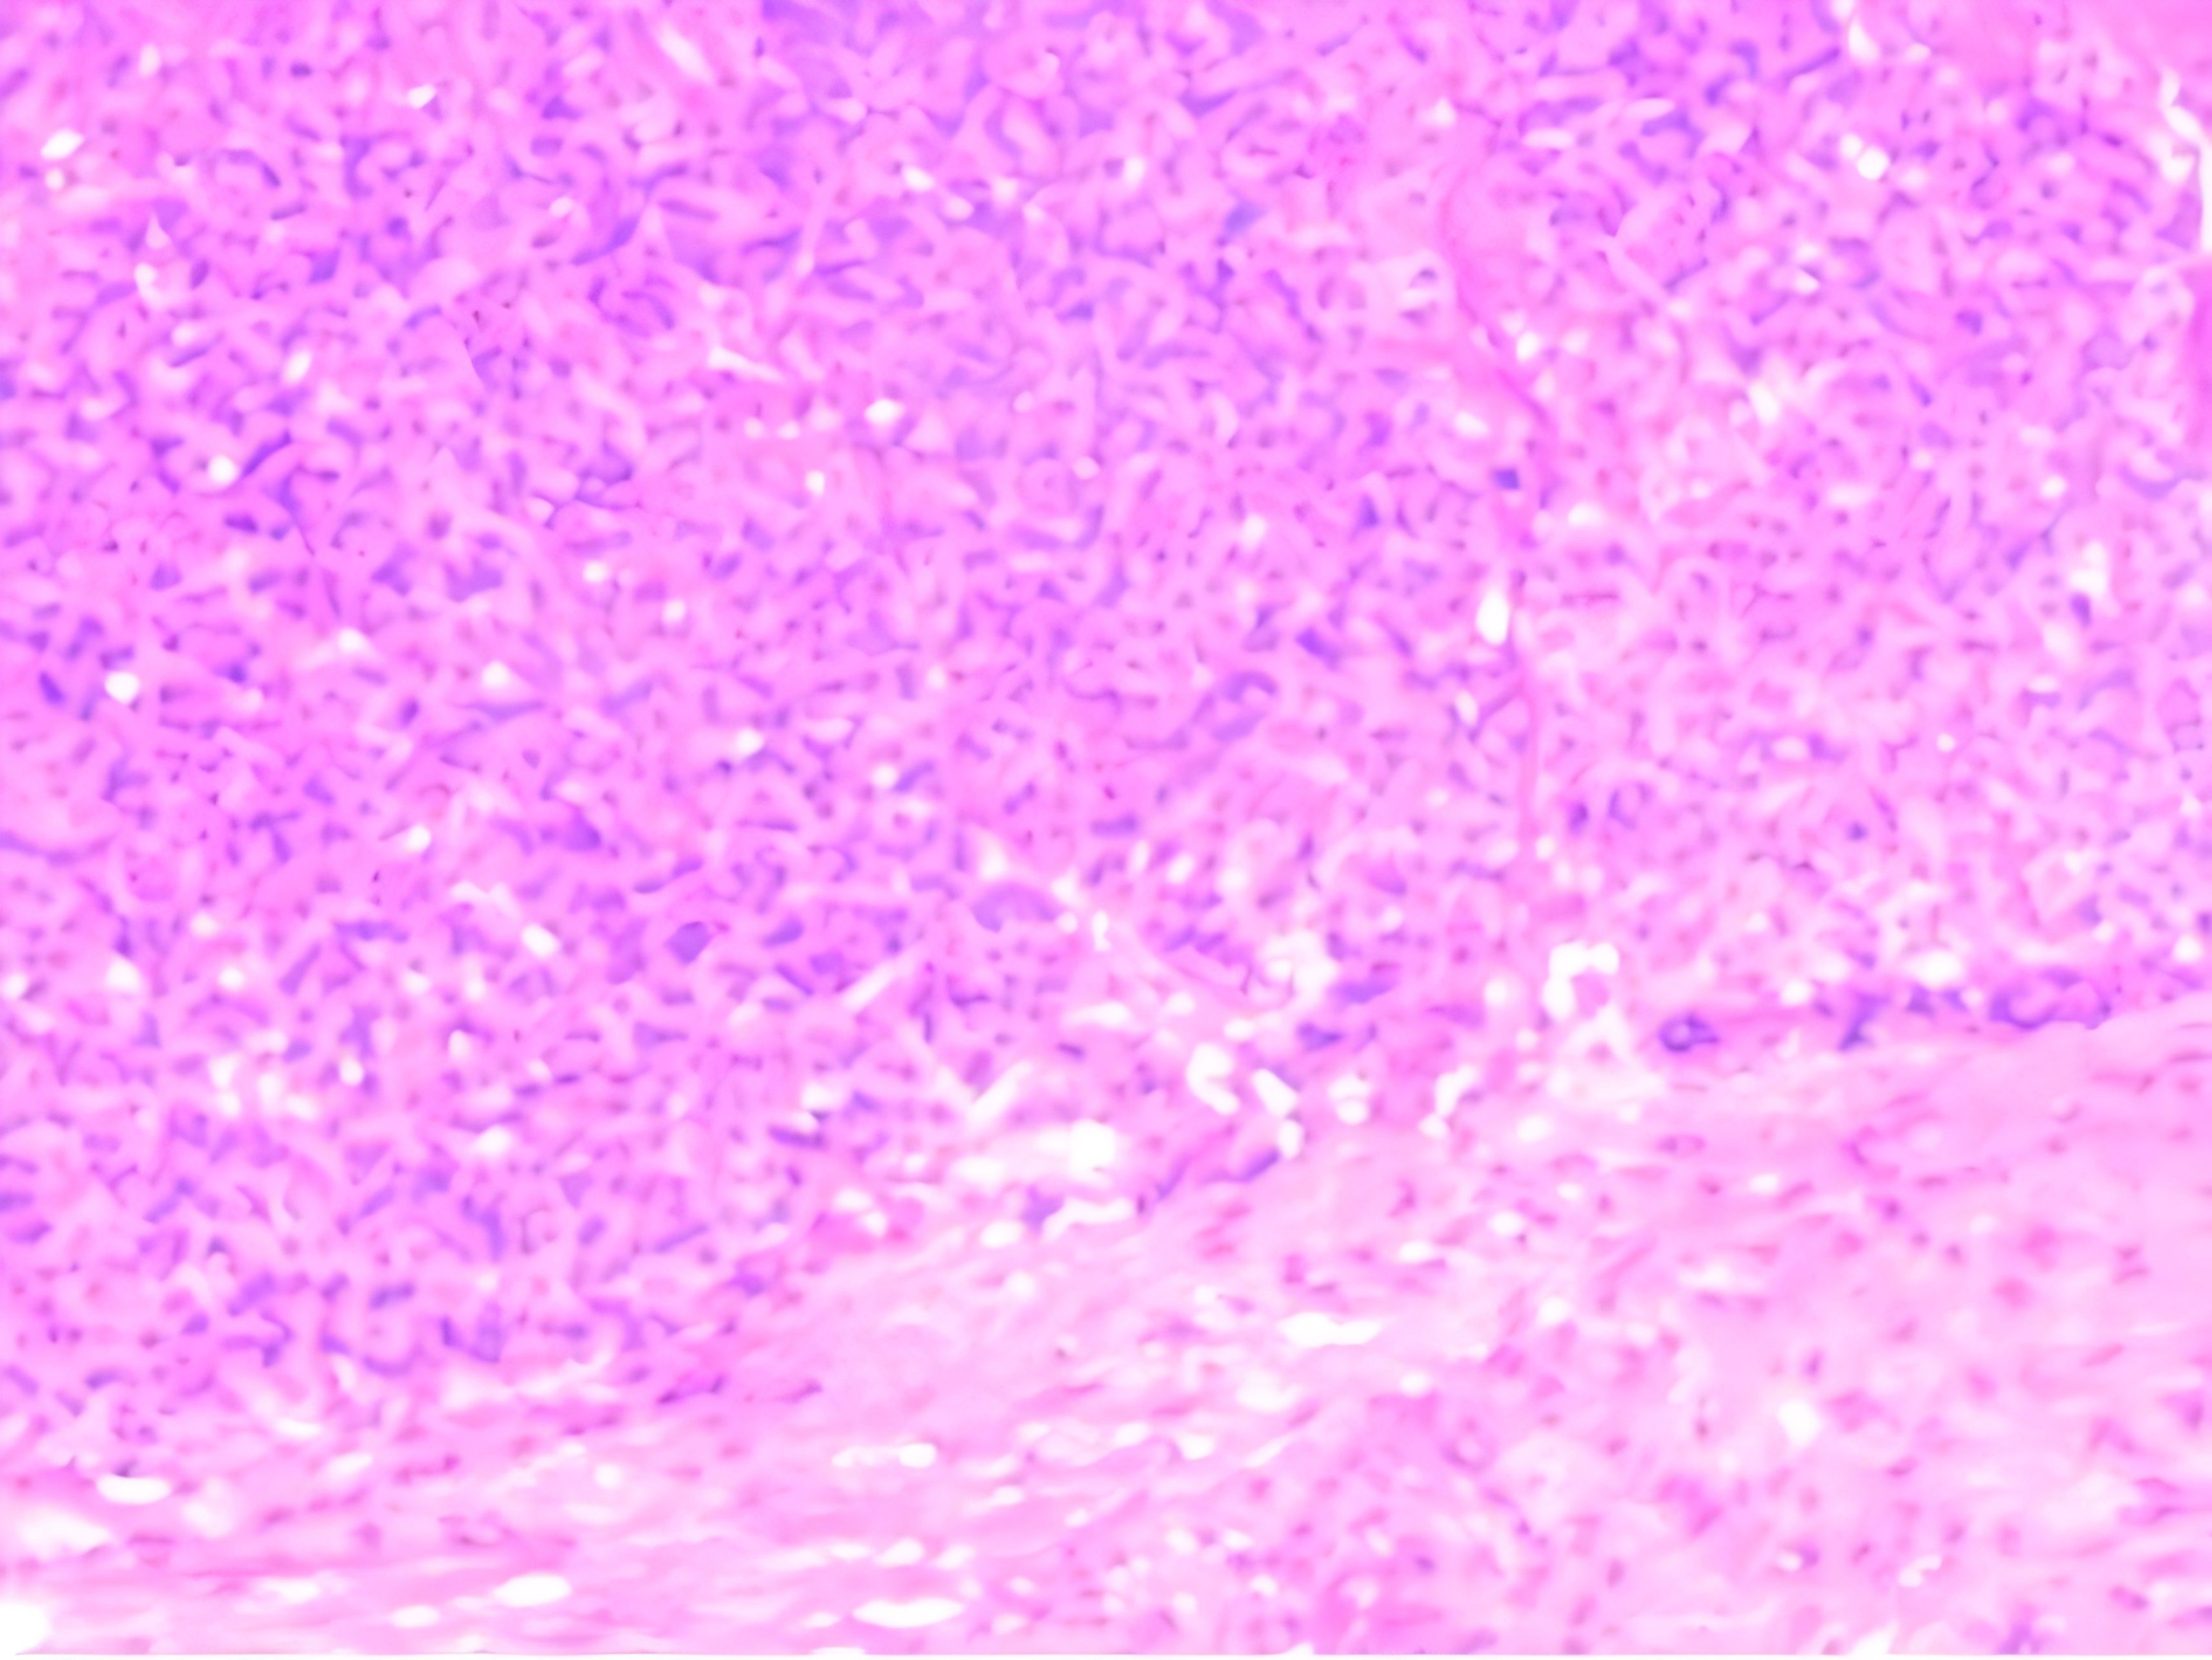

Thereafter, an ultrasound-guided biopsy of the mass was performed. Histopathology revealed that the tumor cells exhibited uniform morphology, with weakly eosinophilic cytoplasm and rich vasculature. No evidence of mitotic figure or necrosis was seen. Immunohistochemistry showed positivity with SMA and Ki-67(<5%), vessel positivity with CD31 and CD34, while negative for S-100, Melanoma, CgA or TFE3. These findings were compatible with the diagnosis of GT(Figure 3). Due to the mass being located within the striated muscle, the pathological diagnosis was GT of uncertain malignant potential.

Figure 3. Histological examination at ×100 objective (H&E stain) showing monotonous small round cells arranged in sheets surrounding vascular channels. The tumor cells demonstrated pale eosinophilic cytoplasm with well-defined cell borders, containing centrally located round nuclei exhibiting homogeneous chromatin patterns. Mitotic figures were conspicuously absent.